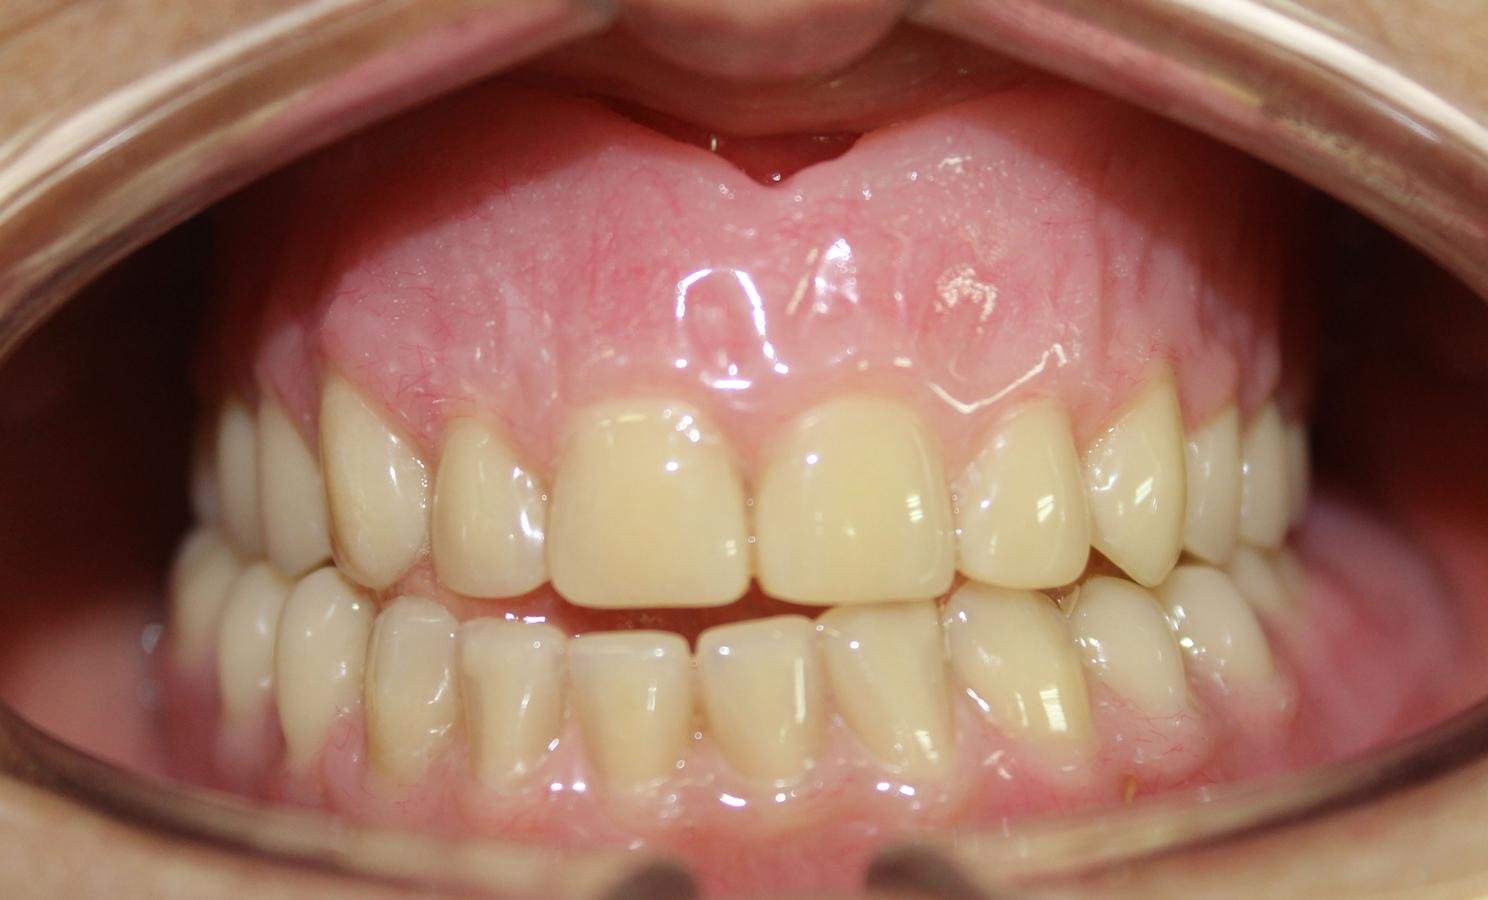

EVOLUCIÓN

7 días después

"Me siento mucho mejor, ahora si puedo comer" Paciente